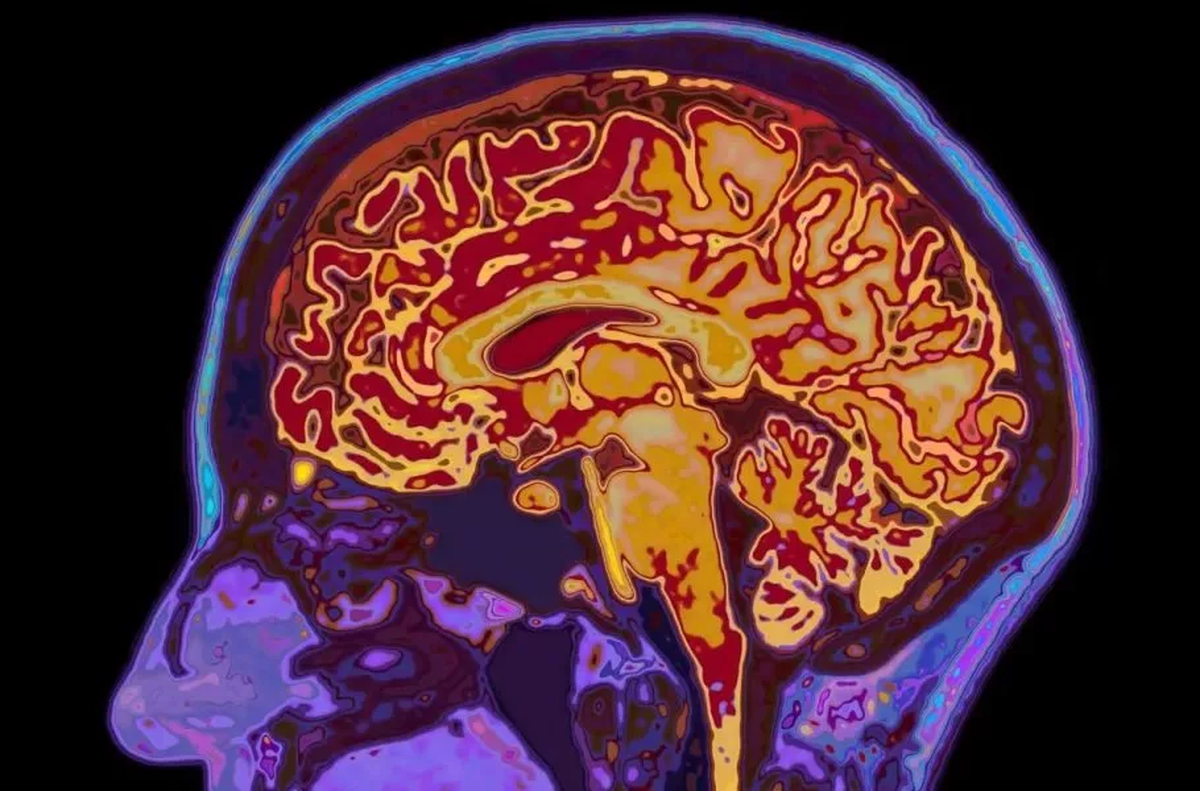

شاید فکر کنید با تمام‌شدن دوران نوجوانی، مغز شما هم به بلوغ و رشد نهایی رسیده است. اما دانشمندان دانشگاه کمبریج این باور قدیمی را رد کرده‌اند. آنها با اسکن مغز ۴ هزار نفر (از نوزاد تا ۹۰ ساله) کشف کردند که مغز انسان نه یک مسیر خطی، بلکه ۵ دوران متمایز را طی می‌کند. محققان می‌گویند مغز ما تازه در اوایل دهه ۳۰ زندگی وارد فاز بزرگسالی می‌شود.

تصور رایج این است که نوجوانی در ۱۸ یا ۱۹ سالگی تمام‌ می‌شود، بااین‌حال مطالعه جدید نشان می‌دهد که مغز تا حدود ۳۲ سالگی همچنان در فاز «نوجوانی» باقی می‌ماند. در این دوران طولانی (از ۹ تا ۳۲ سالگی) مغز مشغول سیم‌کشی مجدد و افزایش بهره‌وری است. این همان زمانی است که بیشترین خطر بروز اختلالات سلامت روان وجود دارد، زیرا مغز درحال تغییرات بنیادین است.

به گزارش گاردین، دانشمندان مراحل رشد مغز را براساس ۴ نقطه عطف مهم (در سنین ۹، ۳۲، ۶۶ و ۸۳ سالگی) تقسیم‌بندی کرده‌اند:

1. کودکی (تولد تا ۹ سالگی): دورانی که مغز به سرعت رشد و اتصالات اضافی را هرس می‌کند.

2. نوجوانی (۹ تا ۳۲ سالگی): طولانی‌ترین فاز رشد که در آن شبکه‌های عصبی کارآمد و سریع می‌شوند. این دوران اوج عملکرد شناختی است.

3. بزرگسالی (۳۲ تا ۶۶ سالگی): دوران ثبات که در آن مغز وارد حالتی پایدار می‌شود. سرعت تغییرات کاهش می‌یابد اما بهره‌وری همچنان بالاست.

4. پیری زودرس (۶۶ تا ۸۳ سالگی): شروع کاهش اتصالات مغزی است. مغز کم‌کم از حالت یکپارچه خارج و به نواحی مجزا تقسیم می‌شود.

5. پیری دیررس (۸۳ سالگی به بعد): مرحله نهایی که تغییرات ساختاری و زوال ماده سفید مغز شدت می‌گیرد.

در این چرخه‌ها سن ۳۲ سالگی اهمیت بسزایی دارد، چون زمانی است که مغز بالاخره آرام می‌گیرد. دکتر «الکسا موزلی» (Alexa Mousley)، محقق ارشد این پروژه، می‌گوید: «درست است که ما در ۳۲ سالگی مثل نوجوانان رفتار نمی‌کنیم، اما الگوی تغییرات مغزی تا این سن مشابه نوجوانی است.» اتفاقات مهم زندگی مانند پدرومادر شدن یا تثبیت شغلی که معمولاً در این سنین رخ می‌دهند، احتمالاً با این تغییر ساختاری مغز هماهنگ هستند.